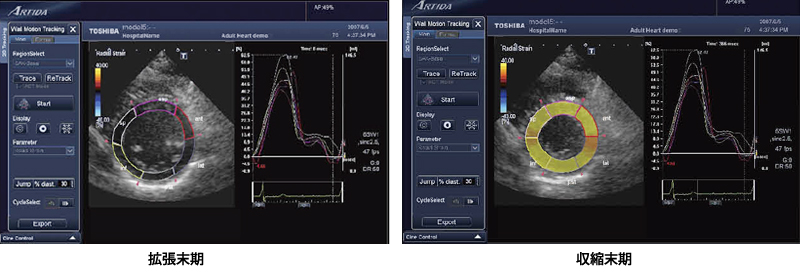

こうしたストレインやrotationの値はカラーコード化され,パラメトリックイメージングとして心筋のBモード像に重畳して表示することが可能である。図5に,実際の2DTによるストレイン解析・表示例を示した。また,ASE,AHAで定められているセグメントごとの各パラメータの平均値についての時間変化をグラフ表示することも可能である。

図5 パラメトリックイメージングとグラフ表示(radial strain)